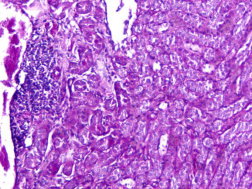

圖1 PAS染色示意圖100×

PAS反應(yīng)陽性物質(zhì) 紅色或紫紅色

細(xì)胞核 藍(lán)色

細(xì)胞質(zhì) 深淺不一的紅色